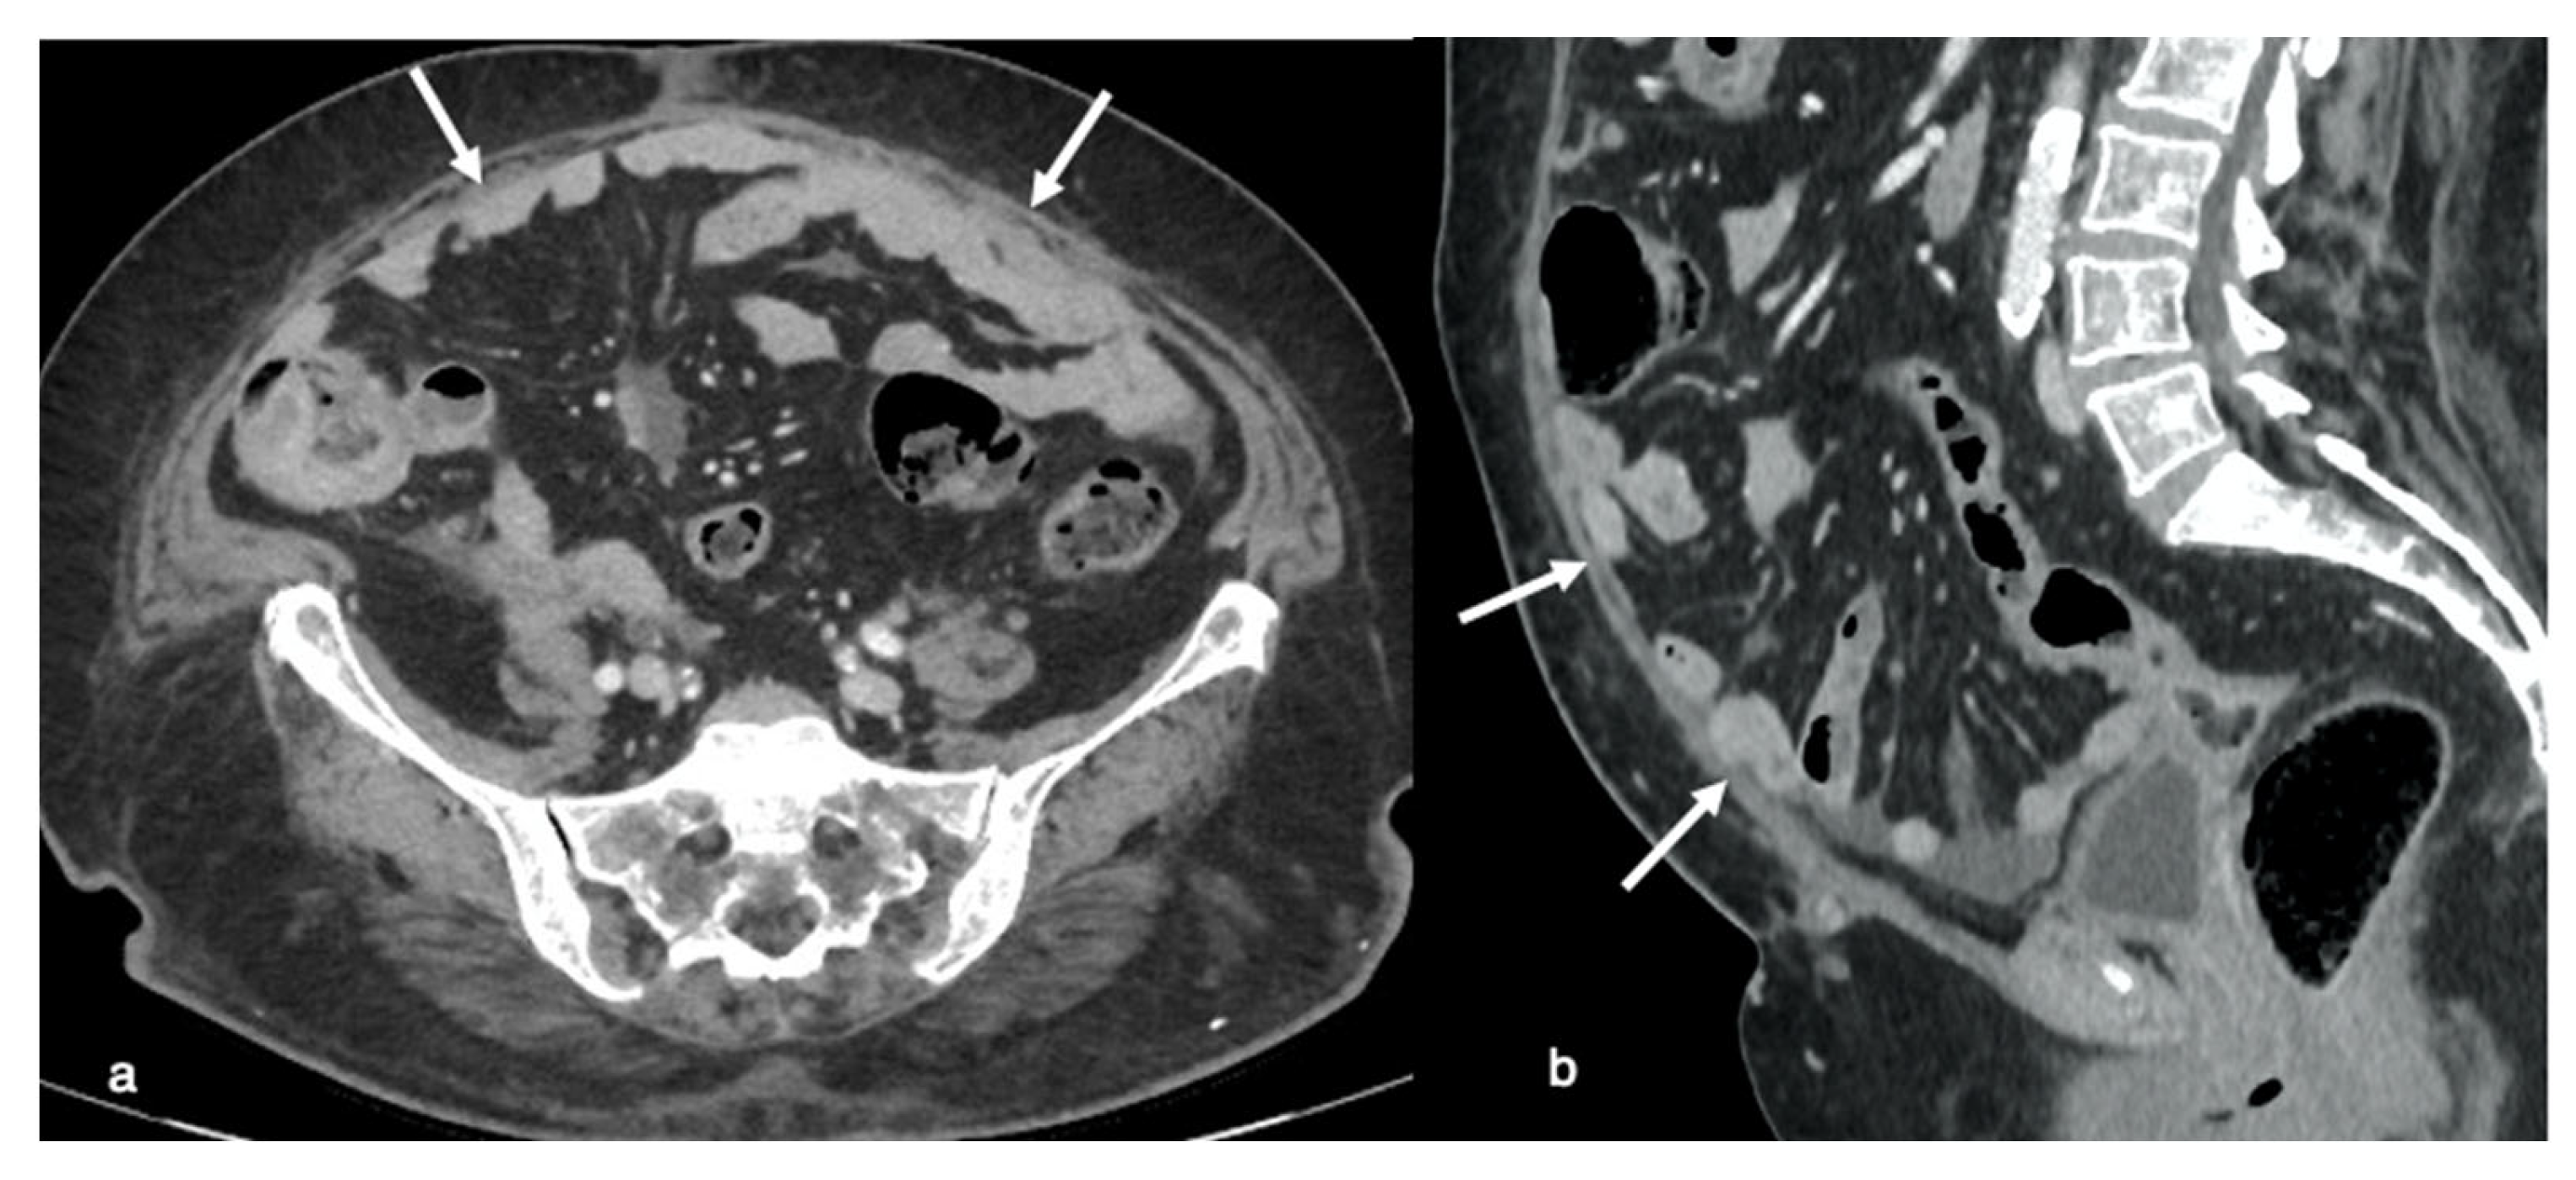

Mesenteric disease may have a wide range of appearances in CT imaging, ranging from generalized penetration (misty mesentery) or clustered small ovoid soft-tissue densities, to confluent, massive, irregular soft-tissue masses characteristically scattered across the superior mesenteric vessels, or affecting both the serosa and the adjacent mesentery. Rigidity and retraction are caused by extensive mesenteric interaction, with contraction of the bowel into the retroperitoneum inducing the clumped form (Figure 5).

The presence of bowel loops and the serosa, both known to be distal components of the mesentery, should be quantified (diffuse bowel involvement with partial obstruction at more than one location or substantial involvement of jejunal regions) where their extensive involvement is linked to non-resectable disease [16]. In comparison, mesenteric root infiltration is considered an absolute criterion of non-resectability.

Figure 5. Infiltration of the mesentery. Axial contrast-enhanced image (a) shows a diffuse infiltration and thickening of mesenteric reflections (arrow) causing diffuse rigidity and retraction of the mesentery, with contraction of bowel toward the retroperitoneum causing a clumped appearance on the coronal CT image (b). Axial contrast-enhanced image shows the “stellate pattern” produced when straightened blood vessels held rigid by the thickened mesentery look like stars in the sky (asterisk in (c)); infiltration of the mesentery can also be represented by nodular visceral peritoneal thickening with multiple small nodules in the mesenteric layers (arrows in (d)).